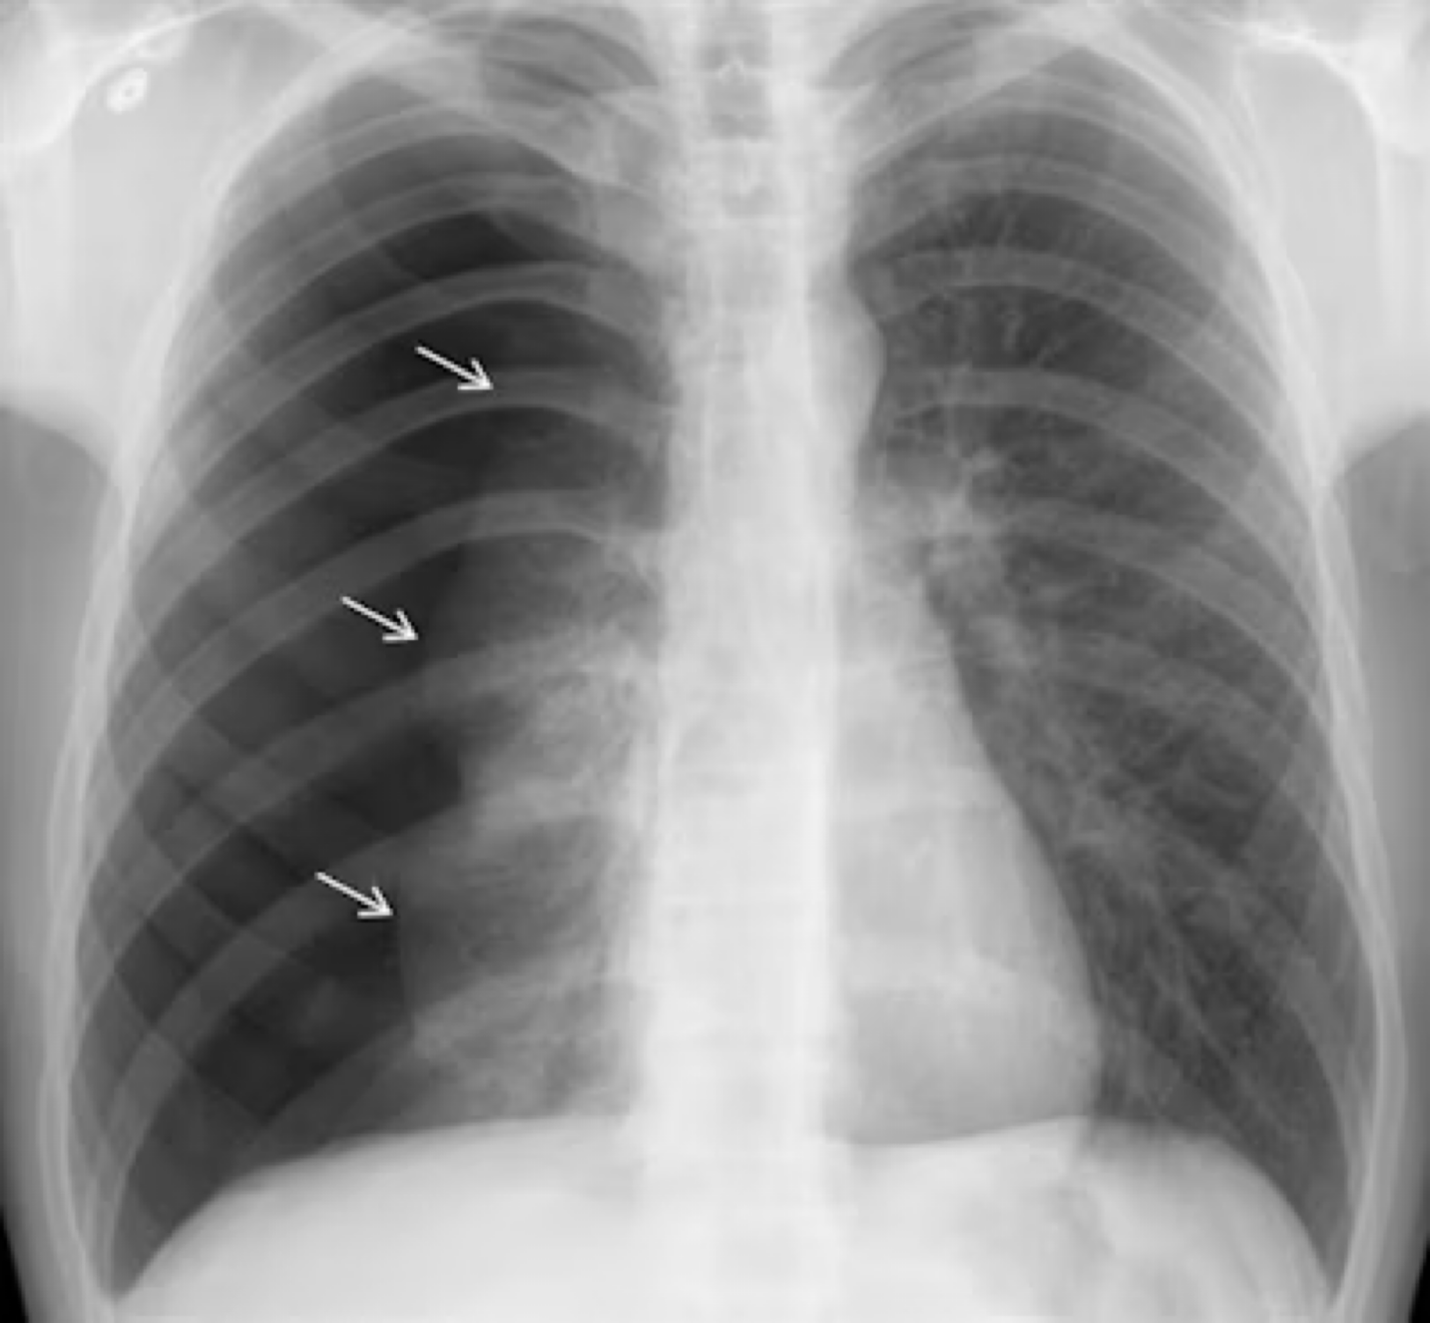

Image: Images courtesy of Dr. Paras Lakhani (https://www.auntminnie.com/imaging-informatics/artificial-intelligence/article/15619315/ai-can-spot-large-pneumothoraces-on-chest-x-ray)

Let’s say Tim came into your ED with atraumatic dyspnea and was found to have a large spontaneous pneumothorax. He’ll need a pigtail or a chest tube, but you’re not sure if there are guidelines around factor replacement in the hemophilia patient who isn’t bleeding yet but will be soon secondary to your procedure.

What is the approach?

Both the WFH and the American guidelines recommend treatment with factor concentrates before invasive diagnostic procedures such as arterial lines, central lines, lumbar punctures, chest tubes, and arthrocentesis. The dose given should be a major dose, enough to elevate their serum factor activity to 100%.